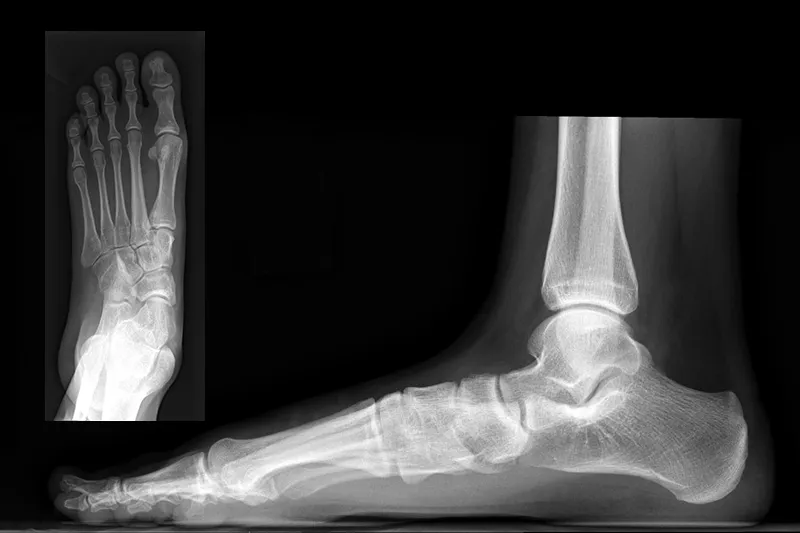

An X-ray image of flatfoot

Novel procedure may bridge the treatment gap for symptomatic flexible flatfoot

A minimally invasive procedure developed in Spain could change the game for patients with symptomatic flexible flatfoot in the U.S.